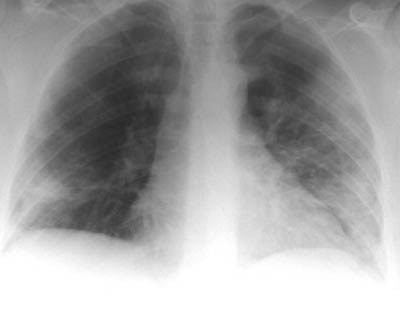

| Radiological signs of SARS include presentation with focal airspace opacity, seen here in the periphery of the right midzone (top image), in approximately 46% of the cases. In 29% of the cases with abnormal radiographs, there were bilateral multifocal opacities (middle image) as well as diffuse opacities, seen here principally in the right lung (bottom image). Images courtesy and copyright of Dr. Narinder Paul, Princess Margaret Hospital, Toronto, ON |

Approximately 25% of the patients are showing normal chest x-rays on admission for SARS, according to Paul. The remaining 75% of patients with abnormal chest x-rays can be divided into two groups.

About 46% of the patients are showing unilateral focal opacities; the remaining 29% are presenting with bilateral multifocal opacities or diffuse opacities. Of these signs, the most worrisome are the diffuse opacities, Paul said, because these patients have shown the highest rate of mortality. Conversations with physicians in SARS-affected areas of China have revealed that these percentages are roughly the same in China, he said.